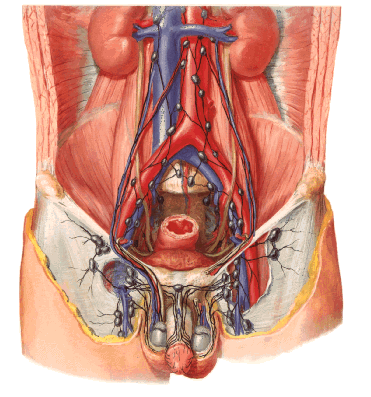

Linfonodos pélvicos retroperitoneais, canalículos linfáticos e linfonodos representados em preto. (associado à figura abaixo)